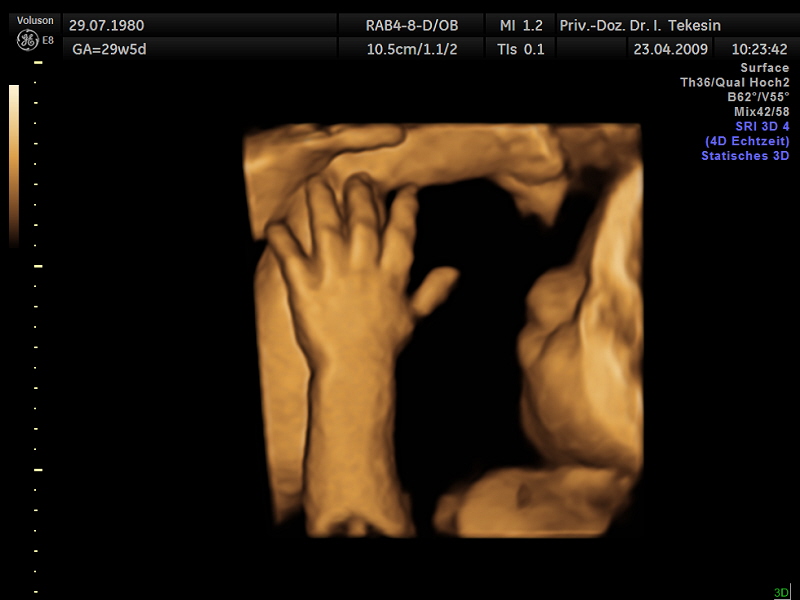

Kind in der 28. Woche (3D-Darstellung)